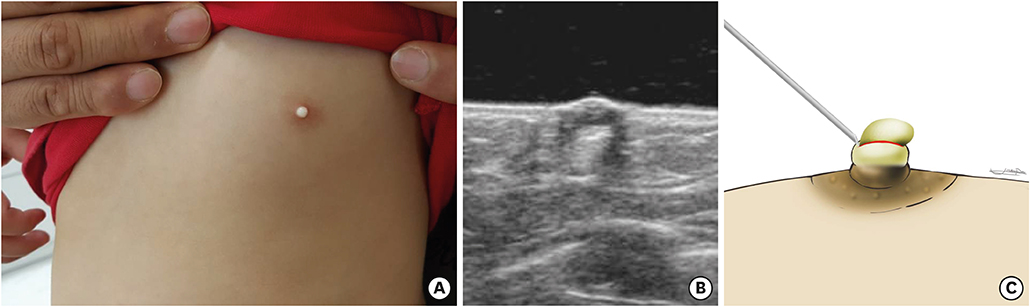

A 32 month-old girl was referred by a pediatrician to a pediatric surgeon in our hospital on account of an abscess-like lesion of the left nipple, which has existed since birth and was similar to ‘witch's milk’. She was born by normal vaginal delivery at gestational age 40 weeks, with a birth weight of 3800g. There had been no traumatic or surgical event on the left nipple in her medical history. The initial finding was a milk-colored tense nontender pustule, which covered the whole surface of the nipple. Ultrasonography showed a 6×5 mm round cyst with no specific connection to the underlying breast. Thus, on the impression of congenital milium of the nipple, incisional evacuation, which squeezes out of inner contents of the mass after incision with the tip of a 23-gauge needle was performed in the outpatient clinic, and the wound remained open (

Fig. 1). Pathologic findings were compatible with an epidermal inclusion cyst showing squamous epithelium with lamellated keratinous materials (

Fig. 1 The congenital milium of the nipple. (A) Gross finding of patient at the first visit. (B) Ultrasonography finding. (C) First operative procedure: incisional evacuation by needle.